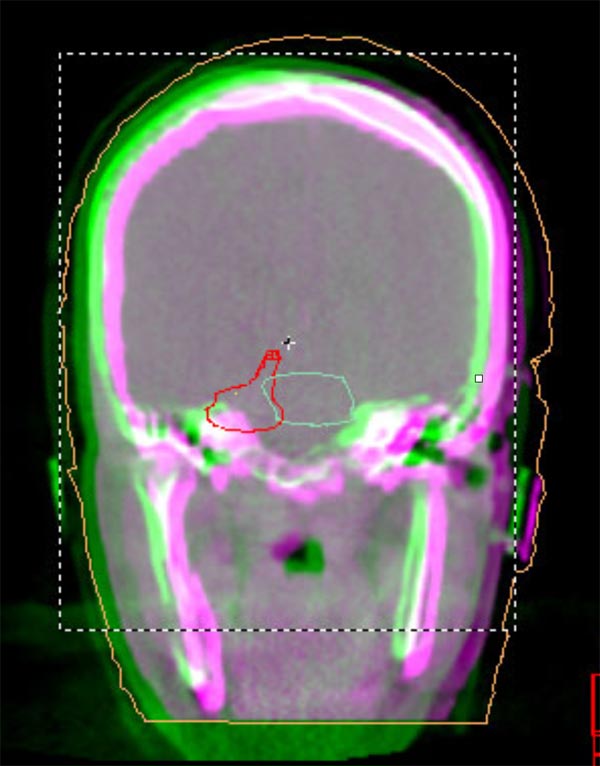

We understand that a cancer diagnosis can be scary, which is why Florida Center for Breast Conservation is dedicated to compassionate care and state-of-the-art technology. Florida Center for Breast Conservation uses the Elekta Synergy® machine, a digital accelerator for advanced image-guided radiation therapy (IGRT). It is the only all-digital treatment device in the world. This allows your doctor to view your tumor in real-time at the time of your treatment.

The 3-D high-quality images taken at the time of your treatment can be studied against your previous CT scans precisely and promptly to ensure that the doctors are treating your tumor as accurately as possible while greatly limiting any exposure to healthy tissue in the area.

Elekta Synergy® provides unparalleled clinical assurance to more aggressively treat tumors while keeping damage to surrounding healthy tissues to a minimum. Elekta Synergy®‘s precision accuracy reduces or eliminates the use of markers because clinicians can view soft tissue using Elekta Synergy®‘s VolumeViewTM. The low-dose imaging proficiency helps minimize the side effects of radiation therapy by decreasing the margins previously set to account for the unpredictability of target location, movement, and dimensions.